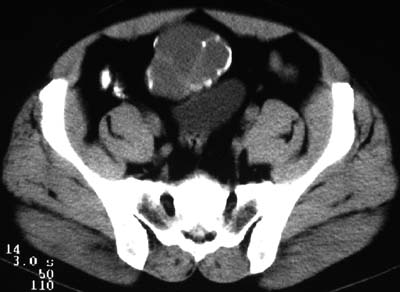

一、女,43岁,下腹部不适,子宫增大并可触及一硬物,活动度大。

典型的盆腔畸胎瘤。

病例1、盆腔畸胎瘤。病例2、盆腔占位压迫膀胱?还是膀胱占位?强化吧!

典型的盆腔畸胎瘤伴子宫肌瘤。

例1:畸胎瘤;

病理1.盆腔畸胎瘤和并子宫肌瘤

病例1、盆腔畸胎瘤,子宫体积增大,子宫肌瘤?病例2,囊腺瘤?

病例1,盆腔畸胎瘤并子宫肌瘤;病例2,囊性肿块,周围有壳状钙化,膀胱受压改变,考虑:脐尿管囊肿并感染,畸胎瘤?

考虑盆腔内畸胎瘤,子宫体积增大,建议增强扫描除外子宫病变